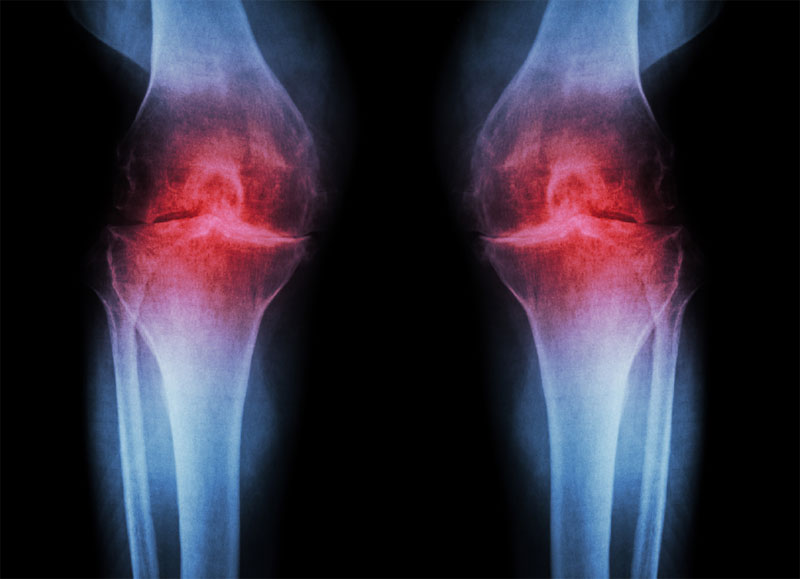

Osteoarthritis

Osteoarthritis is the most common cause of joint pain. It occurs when the protective cartilage that cushions the ends of the bones wears down over time. This leads to pain, stiffness, and swelling in the affected joint.

Knee Osteoarthritis